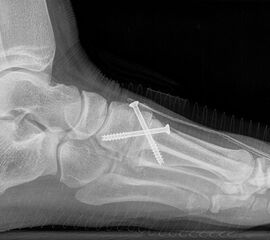

Bezüglich der Operationstechniken wird von früher häufig durchgeführten alleinigen Weich­teileingriffen am Großzehengrundgelenk aufgrund hoher Rezidivraten abgeraten 15. Die Operation nach Mc Bride mit lateralem Release, Exzision des lateralen Sesambeins, Abtragen der Pseudoexostose, Sehnenetransfer des M. adductor hallucis und mediale Kapselraffung zeigte unbefriedigende Mittel- und Langzeitergebnisse 16. Die Cerclage fibreux (mediale Kapselraffung) und das laterale Kapselrelease wird heute in Kombination mit einem knöchernen Eingriff angewendet. Bezüglich des Einsatzes von minimalinvasiven Operations­techniken vor Wachstumsabschluss liegen bisher keine Daten vor. Alle Osteotomien lassen sich nach Bedarf miteinander kombinieren. Es ist darauf zu achten, dass Osteotomien keine offenen Wachstumsfugen verletzen.

• medial aufklappende Cuneiforme I Osteotomie 1522

• Nach Schluss der Wachstumsfugen: TMT I Arthrodese nach Lapidus 2425